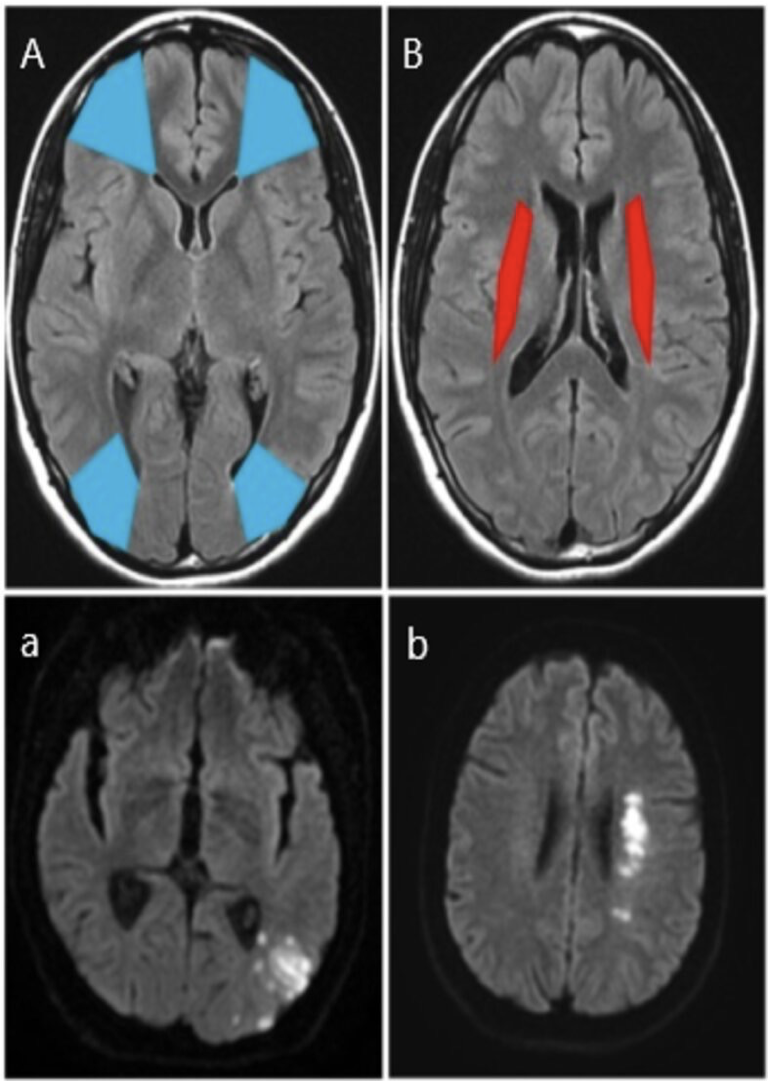

MRI head (A and B: FLAIR; a.and b.; DWI) Cortical border zones, or watershed areas (A; blue), are located between the ACA and MCA territories and the PCA and MCA territories. A left occipital infarct (a; white) is shown at the boundary between the middle and posterior cerebral territories.

Internal border zones (B; red) are located between the superficial and deep branches of the MCA. A left internal watershed infarct (b; white) is shown.